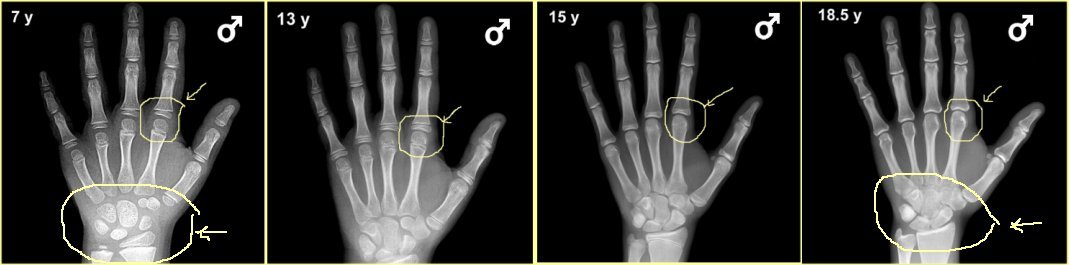

성장판 검사의 목적은 골연령, 뼈나이를 보고자 하는 것입니다

성장판 검사를 통해 성장판이 어느 정도 열려있고, 또 앞으로 얼마의 성장을 보일 것인가에 대한 예측도 중요하겠지만, 성장판 검사의 주 목적은 그 보다는 실제 아이의 나이와 뼈나이, 골연령과의 차이를 보기 위함이 더 큰 것입니다.

또한, 당장의 검사결과수치가 아니라 그 변화과정을 볼 수 있어야하기에 1년에 한 번, 또는 반년에 한 번, 경우에 따라서는 3달마다 검사를 반복하면서 골연령 진행속도를 보면서 성조숙증 여부를 체크할 수 있는 중요한 검사의 하나입니다.